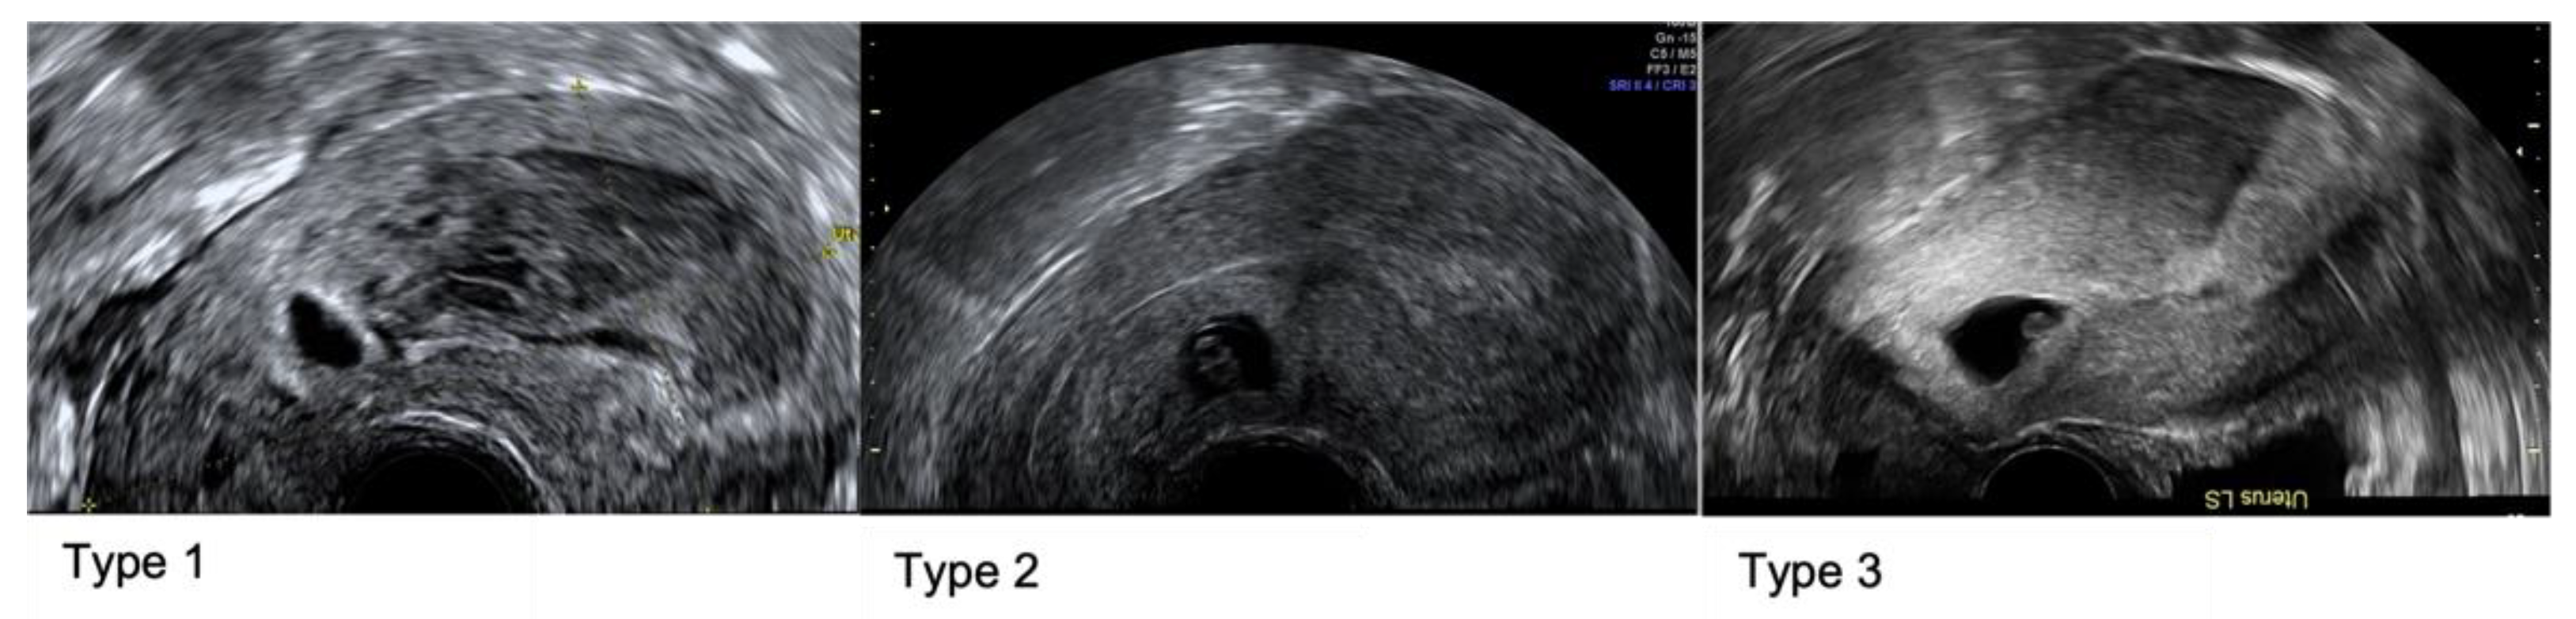

Caesarean Scar Pregnancy (CSP) is an ectopic pregnancy [4] with anterior implantation into the niche of the uterine scar. As per recent Delphi consensus, CSP can be classified as Type 1 where the largest part of the gestational sac (GS) protrudes towards the uterine cavity; Type 2 where the largest part of the GS is within the myometrium not breaching the serosa, and Type 3 where the pregnancy is partially located outside the contour of the cervix or uterus [5].

Initial ultrasound assessments were made by sonographers in a community early pregnancy unit. Low implantation with proximity to the CS scar and an empty uterine cavity and endocervical canal, prompted discussion at the local early pregnancy MDT. Subsequent assessment was then performed by a specialist gynaecology consultant trained in advanced early pregnancy and gynaecology ultrasound. During the specialist ultrasound assessment, the mean size of the GS and CRL were documented if present, and the presence of a yolk sac and/or amniotic sac were noted. In RPOC, the mean size was documented. The colour Doppler flow was described with a score between 1–4 [7] with 1 representing no flow around the pregnancy, 2 minimal flow, 3 moderate flow and 4 significant vascularity. The residual myometrial thickness (RMT) was measured at the level of implantation. The degree of invasion was also described in relation to the uterine serosa. Retrospectively the cases were described as Type 1, 2 or 3 as per recent Delphi consensus (Figure 1) [5].

Figure 1. Caesarean Scar Pregnancy types as per Delphi consensus: Type 1 where the largest part of the gestational sac (GS) protrudes towards the uterine cavity; Type 2 where the largest part of the GS is within the myometrium but not breaching the serosa, and Type 3 where the pregnancy is partially located outside of the contour of the cervix or uterus.